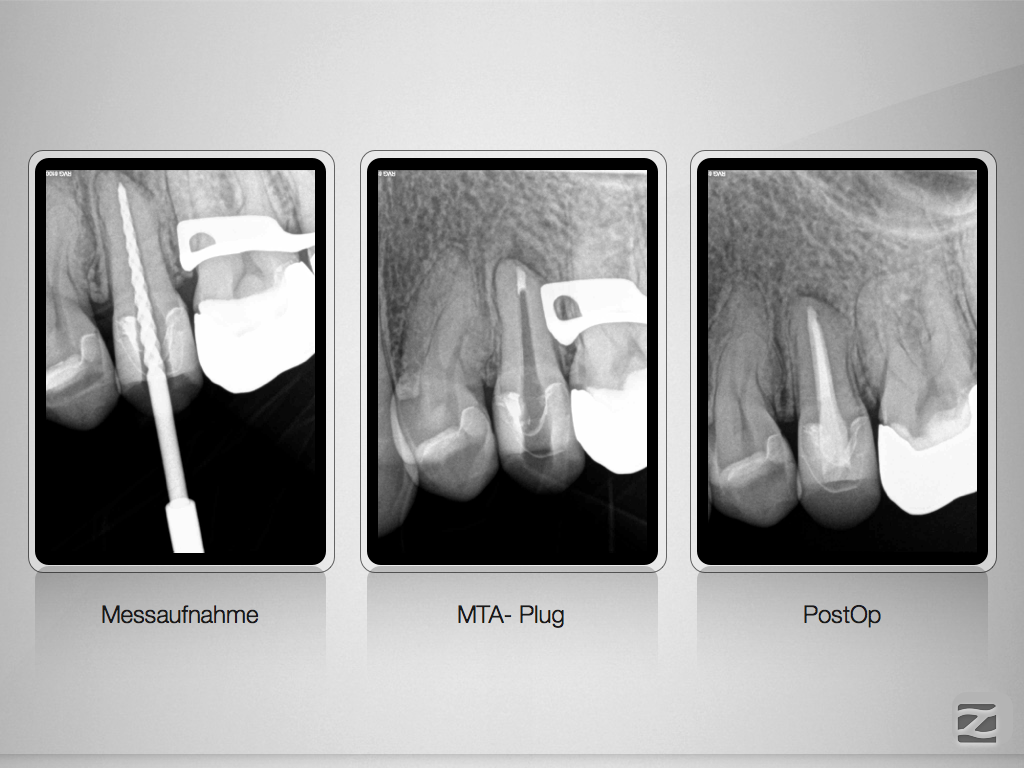

2-in-1 oder unerwarteter Abzweig